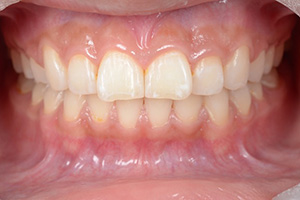

矯正治療のCASE 05

Before

After

-

- 主訴

- 歯並びがガタガタしていて清掃しにくい

- 治療内容

- ラビアル矯正(表側)

抜歯あり

- 治療費用

- 88万円~(税込)

- 治療期間

- 20か月

【リスク・副作用】

歯の痛み、口内炎、歯磨きがしにくいことによるむし歯や歯周病のリスク、歯根吸収や歯の変色、後戻りなどの副作用があります。